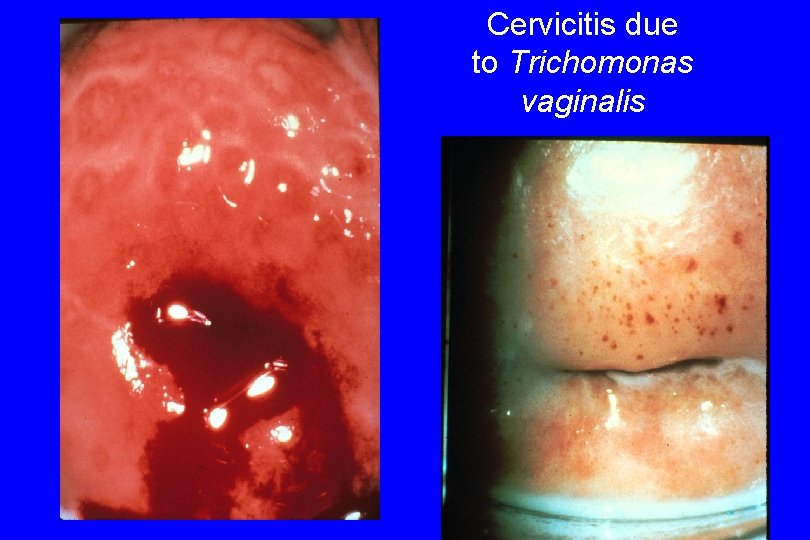

The Cervix and Trichomoniasis l Classic: “strawberry cervix” Ø Focal areas of superficial hemorrhage surrounded by paler mucosa Ø May also see more subtle petechiae Ø More common with relatively moderate-severe Trichomonas vaginitis

Cervicitis due to Trichomonas vaginalis